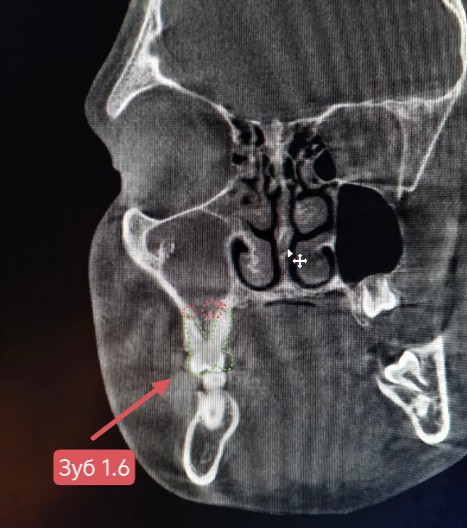

Проведена компьютерная томография околоносовых пазух, которая подтвердила наличие правостороннего гемисинусита (воспаление нескольких пазух с одной стороны), как следствие периодонтита зуба 1.6.

Представлено КЛКТ околоносовых пазух до начала лечения. Выделена зона воспаления пазух.

На снимке детально представлена область пораженного зуба 1.6.